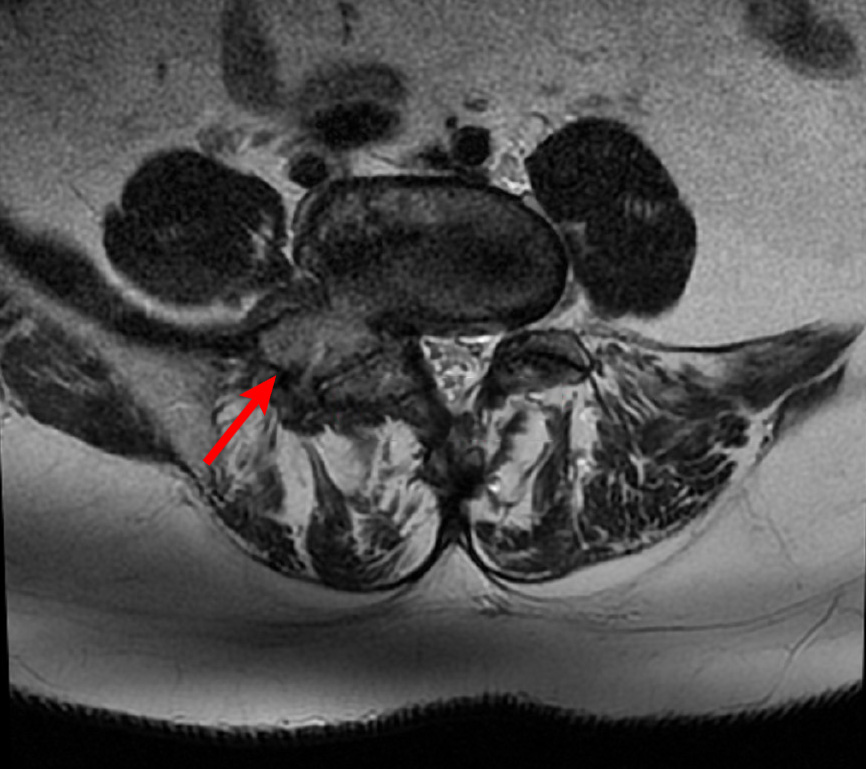

Ασθενής με 2 πολύ μεγάλες δισκοκήλες

Ασθενής 75 ετών με αδυναμία βάδισης λόγω έντονης οσφυαλγίας από έτους. Η αιτία είναι δύο μεγάλες δισκοκήλες που πιέζουν τις εξερχόμενες ρίζες των νεύρων. Με τοπική αναισθησία τοποθετήθηκαν 2 βελόνες στα στα  επίπεδα Ο4-05 και Ο5-Ι1 και έγινε  εισαγωγή μείγματος αναλγητικών. Άμεση ανακούφιση με αποτέλεσμα που διατηρείται 1 χρονο μετά.